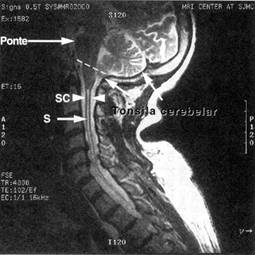

Caso 1 S. M., homem destro de 19 anos de idade, caiu numa calçada debatendo-se em convul-sões. Quando os paramédicos chegaram, as convulsões já haviam cessado, porém, os olhos do paciente estavam paralisados e desviados conjugadamente para a direita. Pouco tempo depois, iniciaram-se movimentos convulsivos no braço esquerdo, assim como, os olhos exibiam mo-vimentos rítmicos e involuntários para a esquerda. Após as crises, e com o paciente já acorda-do, foi realizado exame neurológico, o qual revelou uma discreta fraqueza do lado esquerdo do corpo. A anamnese revelou que o paciente tivera, 2 anos antes, um acidente de moto, no qual sofrera uma contusão frontal direita, o que confirmou o diagnóstico de epilepsia secundá-ria ou sintomática. Caso 2 A paciente era uma estudante de 8 anos de idade. Cinco meses antes, ela desenvolveu uma tendência a tropeçar e cair facilmente quando jogava com outras crianças. Essa falta de equilíbrio progrediu até o ponto de ter dificuldade de caminhar. No inicio, ela caía mais para a frente, e sua mãe relatava que quando a paciente tentava ficar em pé, ela balançava para trás. Contudo, cerca de 5 semanas antes da ida ao hospital, ela tendia a cambalear e cair mais para a esquerda. Desde essa época, ela apresenta tendência de vômito logo após despertar pela ma-nhã, e durante as 4 semanas anteriores ao seu internamento, ela queixava-se de cefaléia nucal e occipital; essa cefaléia piorou progressivamente, associando-se a um estado de desatenção, também progressivo. No dia da admissão ao hospital, a criança relatou que nos últimos dias tinha tido visão dupla. Não havia relato prévio de traumatismo craniano ou história recente de infecção respiratória ou otite. O exame neurológico revelou um andar atáxico com tendência a cair para a frente ou para a esquerda, dismetria nas provas dedo-nariz e calcanhar-joelho e tremor de intenção. Os reflexos tendinosos eram exagerados nos 4 membros e o reflexo plantar era extensor bilateralmente (sinal de Babinski). O exame oftalmoscópico revelou edema de papila bilateral. Havia fraqueza bilateral do músculo reto lateral e nistagmo espontâneo, que piorava na tentativa de olhar lateralmente. Havia também discreta paresia facial esquerda, de modo a não conseguir fechar a pálpebra do olho esquerdo, e a boca tinha discreto desvio para a direita. Não havia febre nem rigidez de nuca. A tomografia computadorizada do crânio revelou processo expansivo da linha média do cerebelo e hidrocefalia por aumento dos ventrí-culos laterais e 3o ventrículo. O paciente não pôde ser operado, vindo a falecer algumas sema-nas depois. A autopsia revelou tratar-se de um meduloblastoma. Caso 3 Uma mulher de 55 anos de idade, outrora saudável, começou a queixar-se de visão turva. Três dias mais tarde, ela despertou sem poder abrir seu olho esquerdo. Foi então hospi-talizada para avaliação. O exame neurológico revelou apenas ptose palpebral completa à es-querda. Quando lhe era levantada passivamente a pálpebra esquerda, evidenciava-se que o olho esquerdo estava desviado para fora. Além disso, ela não conseguia olhar para cima e para baixo com o olho esquerdo. Sua pupila esquerda era maior que a direita e também não res-pondia ao estímulo luminoso direto ou consensual, ou à acomodação. A pupila direita reagia a tudo. A acuidade visual era de 20/20 (normal) em ambos os olhos. Os campos visuais eram completos (normais). O exame de fundo de olho era normal, assim como a sensibilidade cór-nea. Foi realizada então uma angiografia dos 4 vasos (carótidos e vertebrais) que revelou a presença de um aneurisma da artéria comunicante posterior esquerda. Foi realizada clipagem cirúrgica do aneurisma e a paciente teve remissão parcial da paralisia do nervo oculomotor esquerdo. Caso 4 Uma mulher de 39 anos de idade procurou consulta médica por perda de memória e diminuição da visão. Tinha antecedentes pessoais de alcoolismo. Ao vir à consulta, ela estava mal vestida e mal cheirosa. Ela dizia gracejos e era demasiadamente eufórica. O exame neuro-lógico revelou diminuição da acuidade visual (20/80 à direita e 20/30 à esquerda), edema de papila bilateral, distúrbio de memória e cálculo. Foi realizada então uma tomografia computa-dorizada do crânio que revelou uma grande massa expansiva na área subfrontal esquerda su-prida por ramos da artéria oftálmica, sugestiva de meningioma, o que foi confirmado por e-xame histopatológico pós-cirúrgico. Caso 5 Uma mulher de 54 anos de idade queixava-se de cefaléia difusa ao voltar para casa após um show dançante. Suas amigas achavam que sua linguagem “era sem sentido”. No dia seguinte, sua fala voltou ao normal, porém, estava com febre, e por isso, procurou um hospital. Antes, ela tinha estado bem, exceto por ter tido otite média crônica. Na emergência, ela teve uma convulsão, a qual consistia de movimentos no braço e perna direitos e versão de cabeça e olhos para a direita, durando vários minutos. Sua temperatura era de 39ºC. O exame físico revelou uma perfuração da membrana timpânica direita. Ela estava sonolenta, porém, era despertada facilmente. Ela respondia “eu não sei” a todas as perguntas que lhe eram feitas. Os reflexos tendinosos estavam aumentados no braço e perna direitos, e havia sinal de Babinski à direita, hemiparesia direita e hemianopsia direita. Não havia rigidez de nuca nem sinal de Kernig. Foi feita uma punção lombar e o líquido cefalorraquidiano (LCR) revelou aspecto límpido, pressão de 90 mmH2O, celularidade com 6 hemácias e 452 leucócitos/mm3 (30% polimorfonucleares e 70% mononucleares). A glicose era de 65 mg/dl e a proteína total de 66 mg/dl. A coloração pelo gram era negativa. Hemograma e glicemia normais. O EEG mostrava um foco de ondas lentas no lobo temporal esquerdo. A tomografia computadorizada do crânio revelou uma área hiperdensa também no lobo temporal esquerdo. Foram feitas culturas, e iniciou-se o tratamento com penicilina e oxacilina. As culturas foram negativas. Na semana seguinte, ela ficou torporosa com hemiparesia direita. O estudo do LCR revelou 53 leucócitos/mm3 (todos mononucleares), proteína de 24 mg/dl e glicose normal. Preparação com tinta da Índia negativa (para criptococos). Rx do tórax mostrava pneumonia bilateral. EEG com foco de ondas lentas (delta) bitemporal. Nova TC revelou área hiperdensa no lobo temporal esquerdo. As crises parciais e generalizadas continuavam intermitentemente, apesar da medicação anticonvulsivante. A paciente continuava torporosa. Os reflexos plantares eram ambos extensores. Foram retirados os antibióticos e nova punção foi feita, a qual se revelou normal. Seu coma aprofundou-se e ela só reagia ao estímulo doloroso, apresentando uma pos-tura de descerebração. A paciente faleceu 6 semanas após a admissão. O resultado da do-sagem do título de anticorpos para Herpes simplex subiu de 1:4 vários dias após a admissão para 1:64 duas semanas após. Os títulos de anticorpos para outros vírus não subiram. A autóp-sia revelou êmbolos pulmonares e pneumonia aspirativa. Macroscopicamente, o cérebro apre-senta área de destruição e amolecimento no lobo temporal esquerdo. Microscopicamente, havia necrose do córtex do lobo temporal esquerdo, com alguma extensão para a substância branca, infiltrado celular perivascular e glicose. Não foram vistos corpos de inclusão celular. Havia raros focos meníngeos de células inflamatórias. Caso 6 A Sra. J. R. é uma mulher negra, de 67 anos de idade, até então saudável, que veio ao departamento de emergência queixando-se de edema e mobilidade diminuída no seu braço direito. Declarou que há 5 dias notou uma sensação de queimação debaixo da axila direita e fraqueza do braço direito, que persistiu até o momento. Não tem dor. No passado, havia sido submetida a uma cirurgia nos ouvidos, bilateral (diagnóstico não-declarado), e a uma cirurgia bilateral do túnel do carpo. Começou a usar bengala há cerca de um ano, porque passou a mancar. O exame físico revelou temperatura de 95,2ºF, 35ºC, coração a 80 bpm, 20 incursões respiratórias e pressão arterial de 152/82. Paciente bem-humorada, não mostrando sinais de desconforto ou preocupação. Uma cicatriz de queimadura foi observada no ombro esquerdo, que a paciente disse ser resultado do uso de bolsa térmica elétrica, há 10 anos. Não usa mais bolsas elétricas. Sua articulação do cotovelo esquerdo estava muito aumentada e deformada. O exame neurológico mostrou que a Sra. J. R. estava orientada quanto ao lugar, à pessoa e ao tempo. Contava uma história coerente. Não foram observadas anomalias na função dos nervos cranianos. A paciente caminhava mancando ligeiramente, favorecendo o lado direito. Estava firme sobre seus pés. As flexões profundas do joelho e o pular num só pé não foram realizadas. O exame dos sistemas motores mostrou que a força nas pernas da paciente era igual bila-teralmente (5/5). Fraqueza (3/5) e falta de mobilidade no membro superior direito foram ob-servadas. A preensão da mão esquerda era mais fraca que a da direita. Não foram observadas espasticidade ou rigidez. Observou-se atrofia dos músculos interósseos da mão esquerda. Não foram observados movimentos anormais. Do ponto de vista da sensibilidade, havia percepção diminuída bilateralmente da picada do alfinete e da temperatura, da base do pescoço até 2 cm acima do umbigo. A percepção do chumaço de algodão passado sobre a pele era assimilada igualmente nas quatro extremidades e no torso. Era capaz de ficar de pé, sozinha, com os olhos abertos e fechados (teste de Romberg normal). Os reflexos de estiramento muscular estavam ausentes bilateralmente dos músculos bíceps, tríceps e bráquio-radial. Os reflexos estavam aumentados (+) bilateralmente nos músculos quadríceps e gastrocnêmio. O sinal de Babinski estava presente bilateralmente. Os testes calcanhar-joelho e dedo-nariz (braço es-querdo) foram realizados e portanto estavam normais. Não foi observada afasia. Sinais atavís-ticos e o reflexo optocinético não foram testados. Os resultados dos exames de neuroimagem foram os seguintes: 1) As radiografias revelaram fratura com deslocamento da cabeça distal do úmero direito e degeneração grave das articulações do cotovelo esquerdo e do ombro direito (articulação neurotrófica); e 2) A imagem por ressonância magnética do encéfalo e da medula espinhal revelou malformação de Arnold-Chiari e siringomielia da medula espinhal desde a junção cérvico-bulbar até o nível torácico médio (vide figura). O diagnóstico foi então confirmando como sendo siringomielia associada à malformação de Arnold-Chiari.